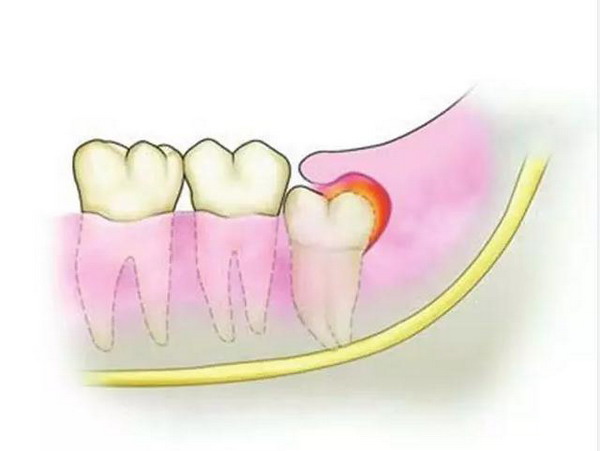

萌出不全的智齿被周围软组织包围,里面的细菌“好吃好喝”不说,还会造成冠周炎。当初小许发誓:“宁愿牙痛痛死,都不愿体验拔牙的痛苦。”而最后,她没有被痛死,而是把自己的牙神经“熬”死了。

北京维乐口腔医院张骞主任表示:“大部分生有智齿的人都会面临像小许这样的困扰,智齿不能完全萌出,其牙冠常被牙龈覆盖住一部分。这个开口就像是扁扁的口袋,学名冠周袋,在进食的过程中,很容易积存食物残渣。”这里有适宜的温度、湿度和食物供给,简直就是细菌的乐园,它们尽情造作的结果就是智齿容易遭遇龋坏和反复的发炎。

大多数人认为智齿不疼就可以不用管了,但即使智齿暂时不疼,也不要大意,它可能引发多种问题。容易滋生细菌、引发龋齿、牙冠损伤、造成牙齿不整齐的现象。而且,阻生的智齿往往不能与对颌牙齿建立正常的咬合关系,长时间可导致颞下颌关节弹响、牙合疼痛,夜磨牙等症状,对青壮年的身心健康影响较大。